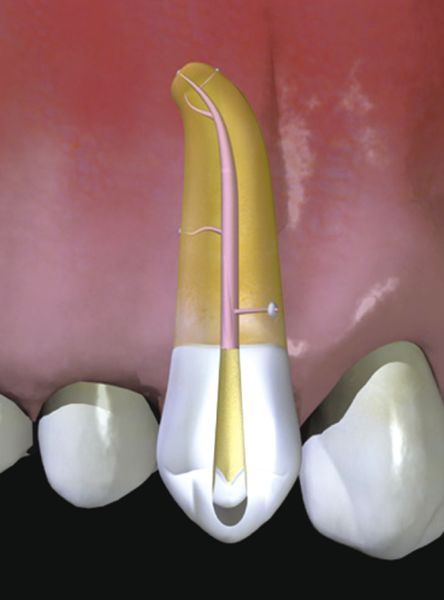

Inside the root of the tooth, there is a cavity called a "root canal" that contains nerves and blood vessels. (Figure 2)

It is easy to understand if you imagine a cream-filled donut.